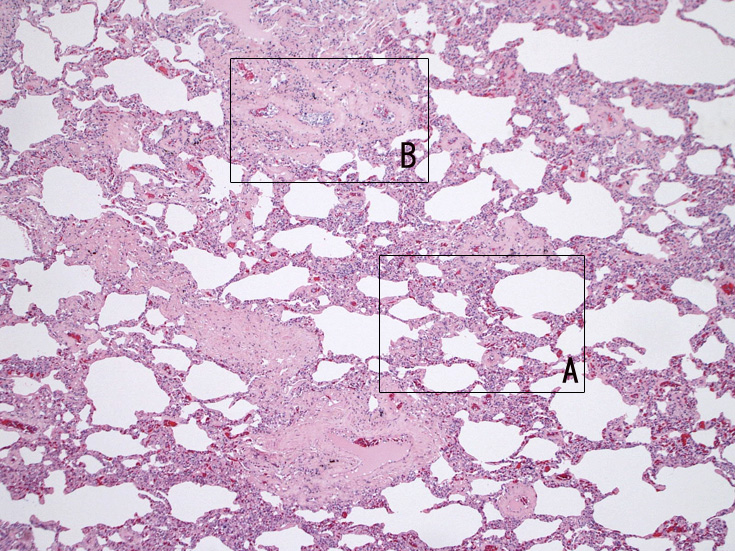

肺A;肺胞壁が厚くなり毛細血管内に腫瘍細胞が多数出現している(A).

肺B;小気管支動脈, 肺動脈内を腫瘍細胞が閉塞する. 動脈内膜に浸潤性増殖している(B)。

肺組織所見